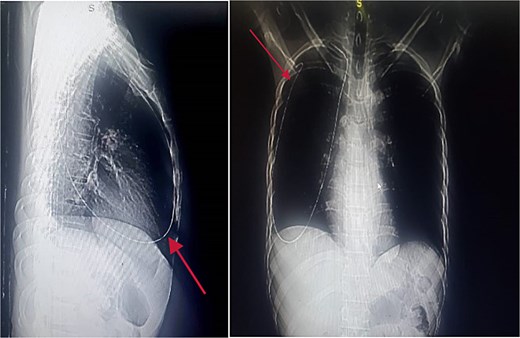

Chest and abdominal X-rays revealed the guide wire extending from the right subclavian vein through the superior vena cava (SVC), right atrium, and inferior vena cava (IVC) to the proximal right femoral vein (Figs 5 and 6).

Plain abdominal X-ray extending from the IVC through the right iliac vein to the right femoral vein.